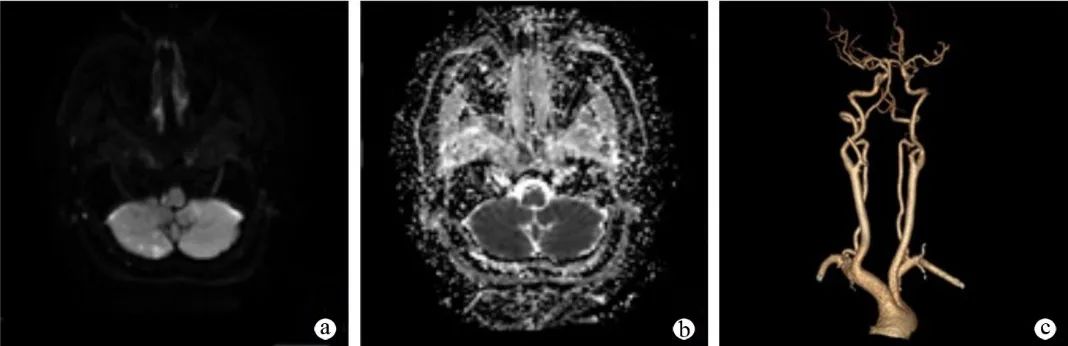

让我们再仔细看一下 DWI:

DWI 提示右侧延髓背外侧小点状高信号,弥散受限,提示急性脑梗死。

a:头颅 MRI 提示右侧延髓外侧部 DWI 序列像可见一类圆形高信号病灶;b:头颈部 CTA 提示右侧椎动脉 V4 段粗细不均,局部管腔扩张;c:颈段脊髓 MRI 未见明显异常;d:胸段脊髓 MRI 未见明显异常。

a:头颅 MRI 弥散成像序列提示右侧延髓外侧及右侧小脑半球 DWI 高信号病灶;b:右侧延髓外侧及右侧小脑半球 ADC 低信号病灶;c:头颈部 CTA 提示双侧颈内动脉虹吸部、椎动脉颅内段及基底动脉钙斑影,伴管腔粗细不均匀,局部轻度-中度狭窄。